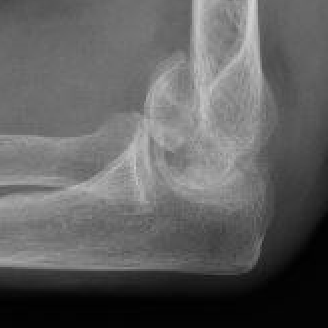

Bryan & Morrey Classification

Type I Type II

Large osseous fracture of the capitellum

Articular cartilage injury with little bone

Hanh Steinthal fracture

Kocher Lorenz fracture